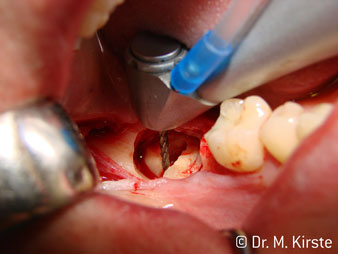

Угол 45° наконечника был выбран специально с учетом широкого круга преимуществ. Коллеги, которые работают в хирургии, и для которых этот наконечник был изначально создан, быстро оценят возможность эффективно работать в очень стесненном пространстве. В частности, при удалении зуба мудрости (рис. 2) не нужно сильно раздвигать мягкие ткани в области щеки (рис. 3). Конструкция головки наконечника в сочетании с небольшим поворотом головки во время препарирования позволяет быстро и безопасно выполнять работу в области задних коренных зубов.

Профессиональная конструкция подшипников внутри головки обеспечивает тихую работу бора; впечатляет атравматичное разделение зуба и корня (рис. 4-9).

Угловой наконечник с углом 45° очень удобно держать в руках. Вы почти сразу отметите, что рабочая головка имитирует угол наклона вашего указательного пальца, поэтому нужное движение легко переносится на пару воображаемых сантиметров параллельно кончику (рис. 1)".